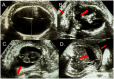

Methodology/principal findings: We report a case of a 20-year-old pregnant woman who was referred to our service after a large Zika virus outbreak in the city of Salvador, Brazil with an ultrasound examination that showed intrauterine growth retardation of the fetus at the 18th gestational week. Ultrasound examinations in the 2nd and 3rd trimesters demonstrated severe microcephaly, hydranencephaly, intracranial calcifications and destructive lesions of posterior fossa, in addition to hydrothorax, ascites and subcutaneous edema. An induced labor was performed at the 32nd gestational week due to fetal demise and delivered a female fetus. ZIKV-specific real-time polymerase chain reaction amplification products were obtained from extracts of cerebral cortex, medulla oblongata and cerebrospinal and amniotic fluid, while extracts of heart, lung, liver, vitreous body of the eye and placenta did not yield detectable products.